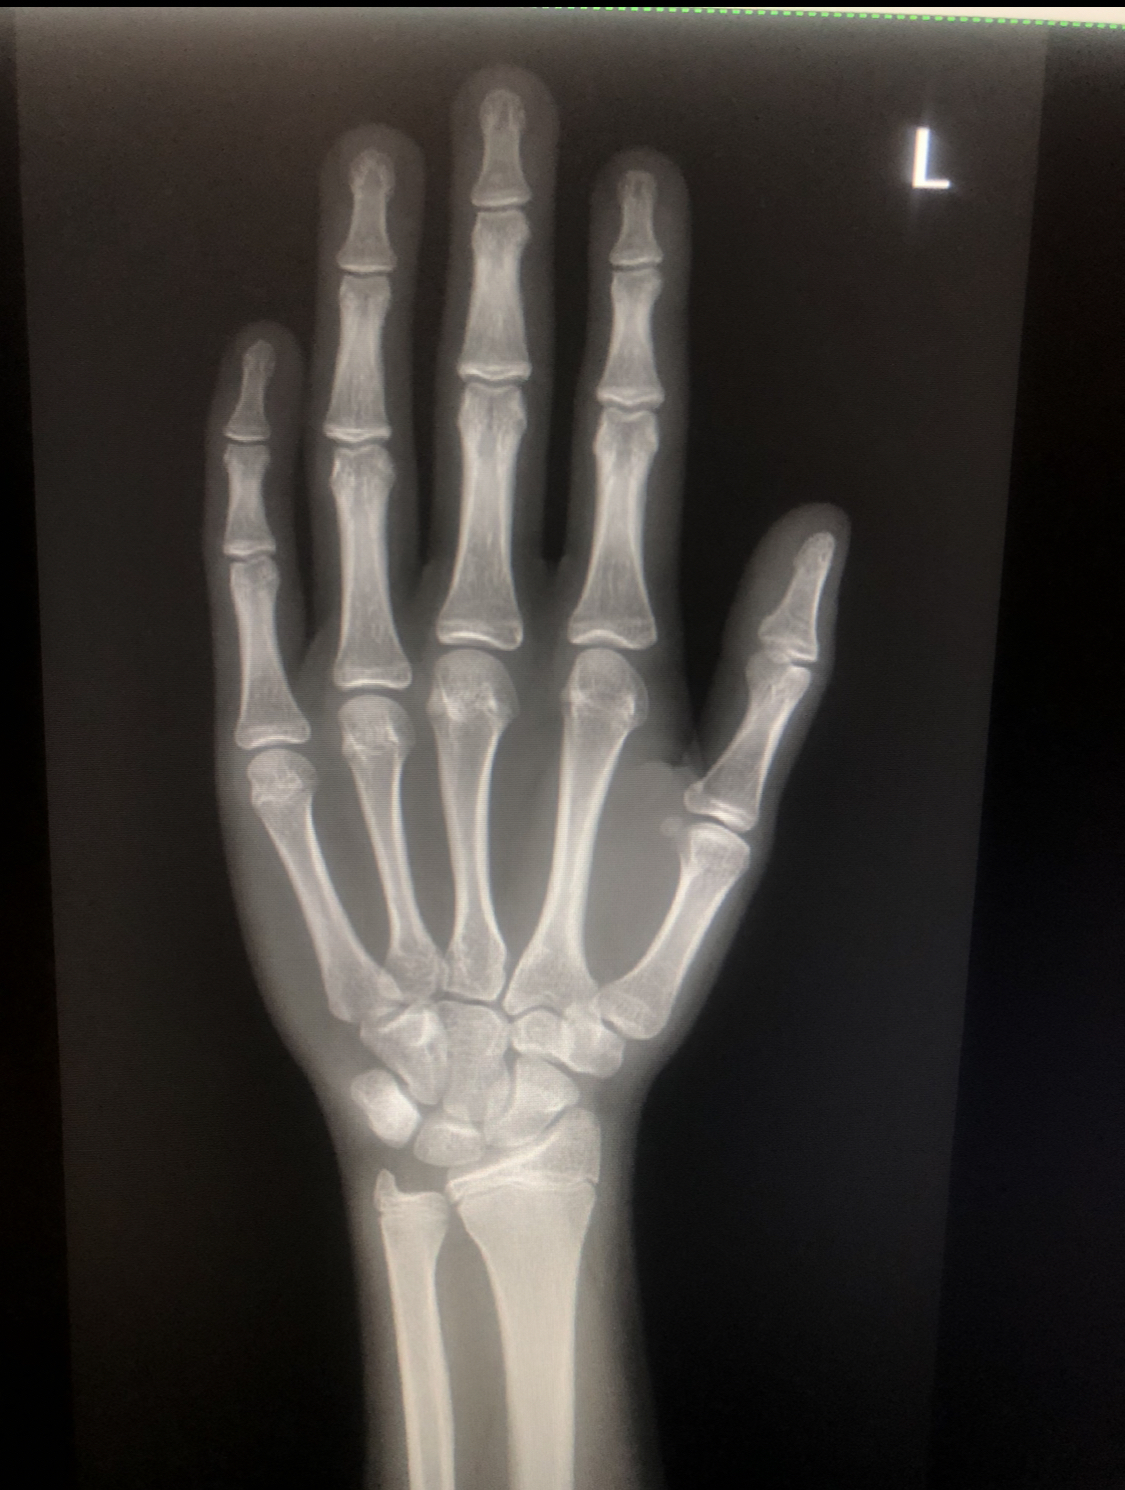

I have been diagnosed with ghd like 2 momths ago and my do prescribed me near 2mgs daily said ur plates wre open first pic and i did an xray again of wrist they were almost fused said its counted as fused and i did my e2 (estradol) it was 50.81ml is it the main cause of my plates fusing so doon at near 16? Tryna get prescribed ai for it

I have been diagnosed with ghd like 2 momths ago and my do prescribed me near 2mgs daily said ur plates wre open first pic and i did an xray again of wrist they were almost fused said its counted as fused and i did my e2 (estradol) it was 50.81ml is it the main cause of my plates fusing so doon at near 16? Tryna get prescribed ai for itView attachment 4929786